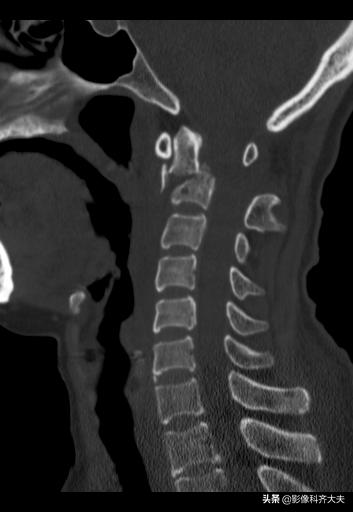

枢椎骨折

枢椎骨折矢状面重建